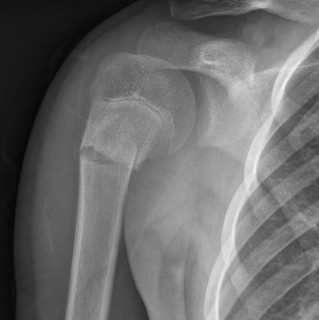

Case: 18 year old boy

Initial xray 18 month xray